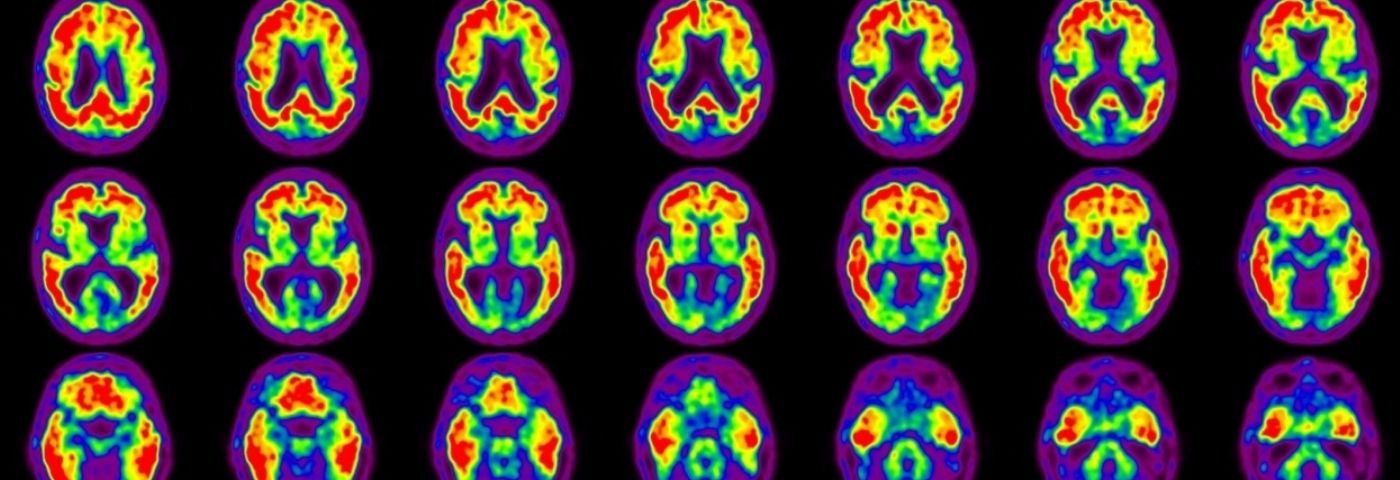

This includes a clinical evaluation, memory and cognitive testing, and brain imaging (such as MRI, CT, or PET scans). Even with these technologies, three in 10 Alzheimer’s cases are not accurately diagnosed compared to other dementias.